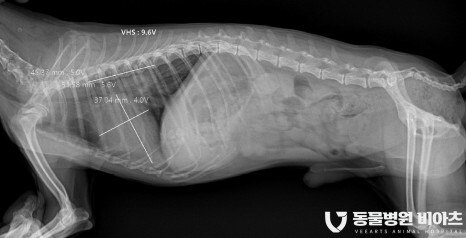

4. 엑스레이/초음파

엑스레이 (VHS, VLAS)

방사선 촬영

방사선 촬영에서는

심장의 비대 정도

VHS(Vertebral heart size) 와

VL(Vertebral left atrial size)

를 측정합니다.